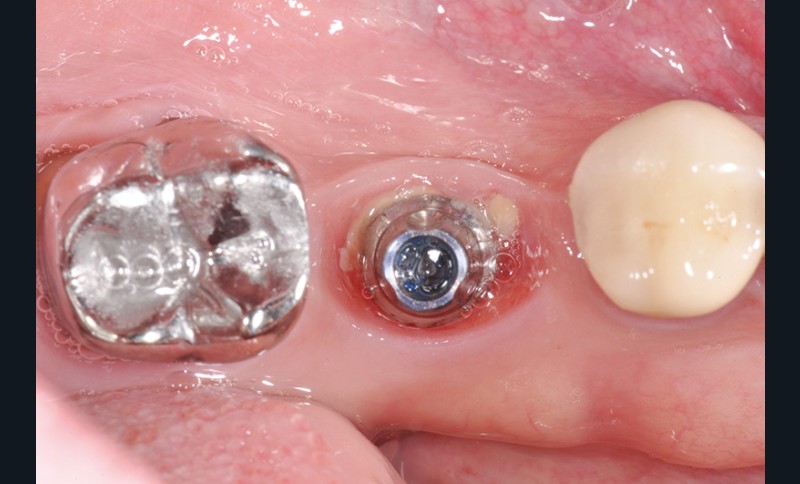

La stabilité des tissus mous autour des implants apparaît également comme un facteur très déterminant. L’absence de barrière kératinisée stable crée une mobilisation haute des tissus jusqu’au col implantaire. Cela a pour conséquence l’apparition de déhiscence gingivale, puis la disparition de l’os vestibulaire ou lingual.

La surface implantaire, ainsi exposée, fait office de porte d’entrée bactérienne. L’état de surface et sa capacité à fixer plus ou moins facilement les bactéries jouent alors un rôle primordial dans l’évolution de la pathologie.